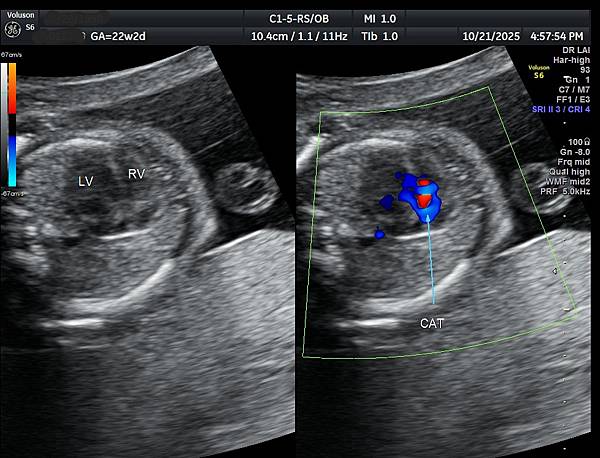

孕婦告訴我們第二胎(2024年10月)也是在孕兒診所檢查,因為胎兒心臟檢查出胎兒有血管環(附圖1,動脈導管在氣管右側,主動脈弓在氣管左側,參考第446篇文章),建議抽羊水做晶片檢查,結果胎兒是狄喬治症候群( 附圖 2. ),當年她已抽24000元的NIPS( 附圖 3.)沒有異常發現(包含狄喬治症候群),這一胎她直接抽羊水,還好檢查結果正常。